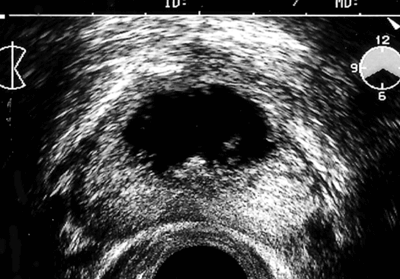

Figure 2: Transrectal ultrasound pre and post GreenLight vaporisation.